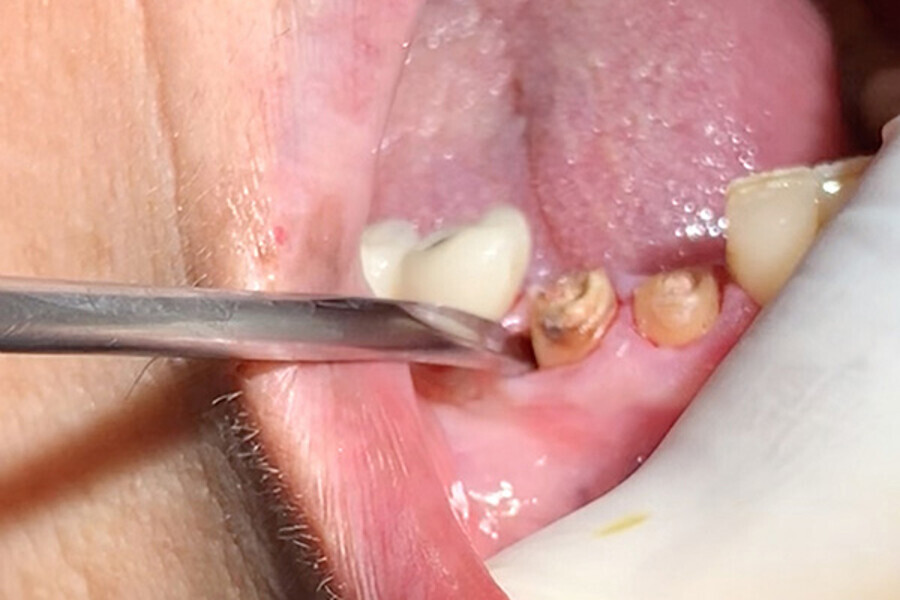

Figs. 4. Uso de los finos insertos para crear espacio entre hueso, ligamento y diente.

Figs. 5. Uso de Botador fino para complementar la luxación.